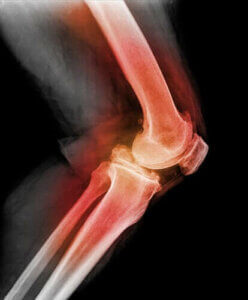

膝蓋骨脱臼の診断を行う時には、医師は膝蓋骨に触れながら膝を曲げ、膝をさまざまな方向に動かします。 レントゲン、MRI(磁気共鳴画像法)、またはCT検査(コンピューター断層撮影)を行うことで膝蓋骨脱臼やその他の膝の怪我の画像を見ることができます。